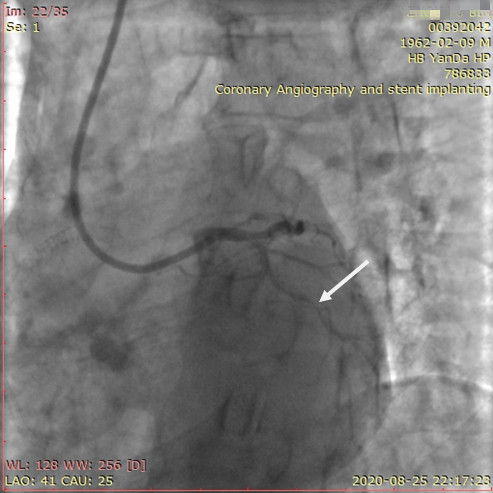

李先生右冠術前影像

術前,翟光耀主任還親自為李先生復查冠狀動脈造影,造影結果顯示:患者的前降支、回旋支、右冠等冠脈三支嚴重病變、嚴重鈣化,且均為彌漫性長病變,最重處99%以上管腔極嚴重狹窄。翟主任仔細閱讀造影結果后指出:結合李先生的實際情況,雖然微創介入手術難度比較大,但仍可行;李先生心臟三支主干動脈均存在極其嚴重的狹窄,每一支動脈均至少植入2-3枚支架,根據患者的耐受情況,李先生可能需要分3次分別對三支動脈進行介入手術;考慮到李先生路途遙遠,病情嚴重,不宜反復奔波,并且患者迫切要求能夠徹 底解決病痛,在病情允許的情況下,如果手術順利,爭取為患者進行“一站式”手術,一 次 性解決全部三支動脈病變!

李先生足位術前影像

李先生足位術后影像

手術方案確定之后,在心血管內三科趙景新主任、介入醫學科富孝晨主任的配合下,翟光耀主任親自擔任主刀,分別依次對李先生的三支動脈進行了完全血運重建。由于手術進展順利,李先生術中沒有任何癥狀,耐受良好,于是成功的將三支動脈“一站式”治療!術中,由于李先生左主干遠端分叉處存在嚴重病變,翟光耀主任選擇國際指南推薦的DK-mini-Crush技術,確保了分叉處兩支主干開口均萬無一失。據悉,DK-mini-Crush技術是目前冠脈分叉病變領域最為復雜及難以掌握的介入技術之一,對手術醫生經驗、體力均提出了極大的挑戰。極為擅長復雜介入技術的翟光耀主任卻用嫻熟的技術確保了李先生手術的成功。

冠狀動脈嚴重鈣化合并狹窄病變是冠脈介入的一大難題,血運重建難度大,成功率低,并發癥發生率高,該例患者的成功救治標志著我院冠脈介入水平又躍上了一個新的臺階。